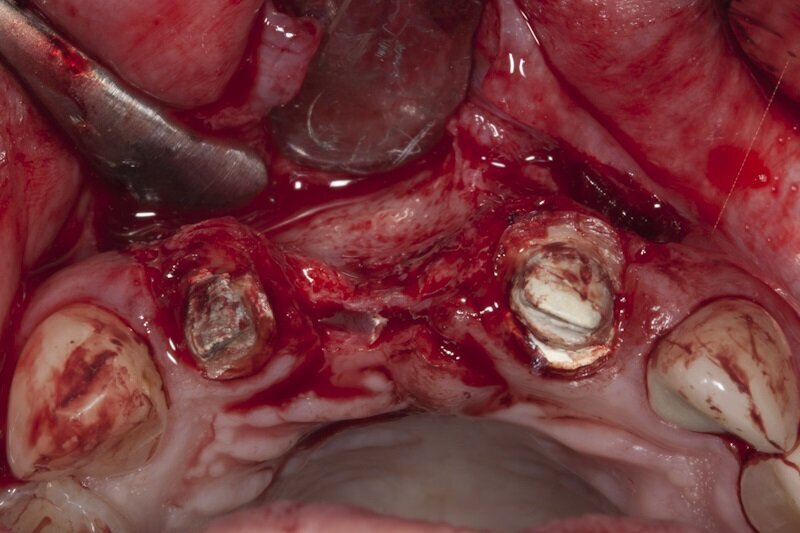

Po kolejnych 4 tygodniach wykonano zabieg bocznej regeneracji kostnej wyrostka zębodołowego w okolicy utraconego zęba 11 w przygotowaniu do przyszłej implantacji (Ryc. 9-11). Zastosowano biomodulację przy użyciu głowicy Genova, na rycinie 12 pokazano stan tkanek 3 tygodnie po zabiegu.

Ryc. 10_Zabieg regeneracji kostnej.

Ryc. 11_Zabieg regeneracji kostnej.

Ryc. 12_Zabieg regeneracji kostnej.